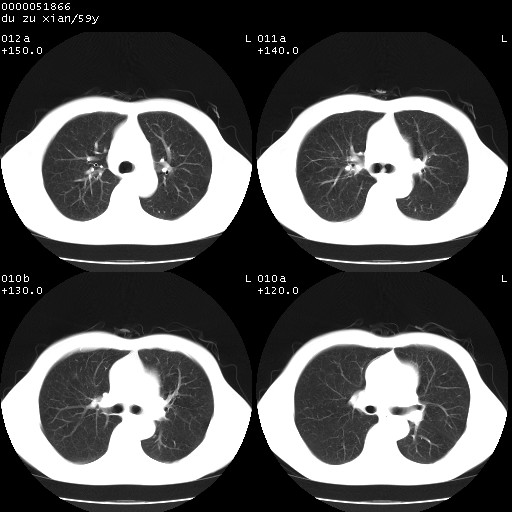

以下是引用宇宙ct在2008-8-25 23:21:00的发言:[br]右肺周围性肺癌并肋骨转移,纵隔淋巴结转移。

以下是引用zsl6918在2008-8-25 22:40:00的发言:[br]右肺周围性肺癌并肋骨转移,纵隔淋巴结转移。

以下是引用zy_zj在2008-8-26 15:24:00的发言:[br]单从病变本身,我倾向良性炎性病变,但肋骨转移了,所以说是考虑右肺周围性肺癌并肋骨、纵隔淋巴结转移可能性大。